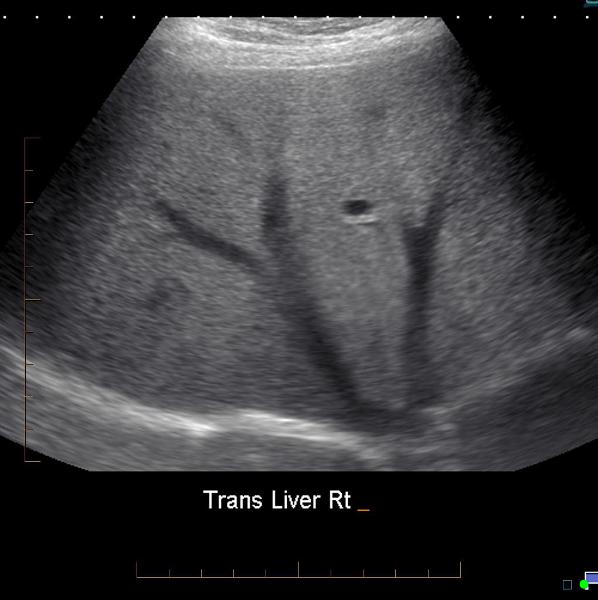

Explain the procedure of a liver exam.

Begin doing a full sweep through the liver. Starting sagittal,

slightly to the left of midline. Change to a transverse view and sweep

up and down the left lobe from a subcostal approach. Look in

transverse through the right lobe subcostally or

intercostally.

Explain the Transverse plane for the liver exam.

The transducer should be angled in a steep cephalic direction to be as parallel to the diaphragm as possible. The transverse plan allows images of liver parenchyma, vascularity and ductal structures.